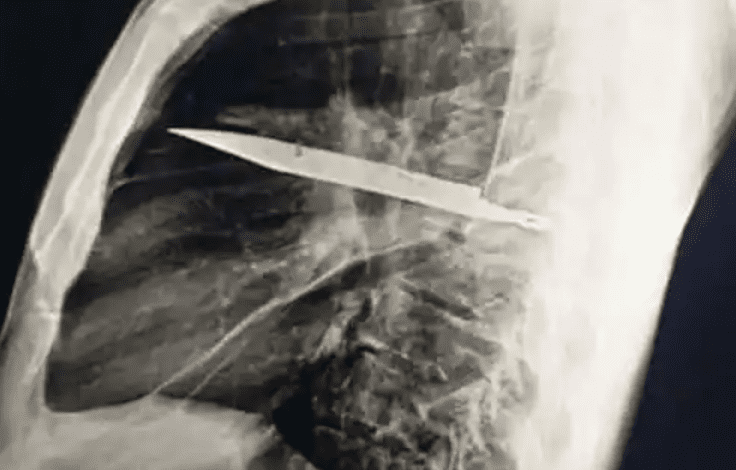

經X光影像檢查,醫師赫然發現一片長約 10 公分的刀刃自右肩胛骨區域斜插入胸腔,巧妙避開心臟、肺葉等重要器官。更令人驚異的是,這片金屬異物在患者體內存留期間,僅因近期組織壞死導致膿液滲出才被發現。

主刀醫師表示,手術成功取出鏽蝕刀刃並清除壞死組織後,患者恢復狀況良好,24 小時內即由加護病房轉入普通病房。醫學專家分析,此案例的特殊性在於異物位置恰好避開主要血管與臟器,加上人體組織的包覆作用,才使患者長期未覺異常。